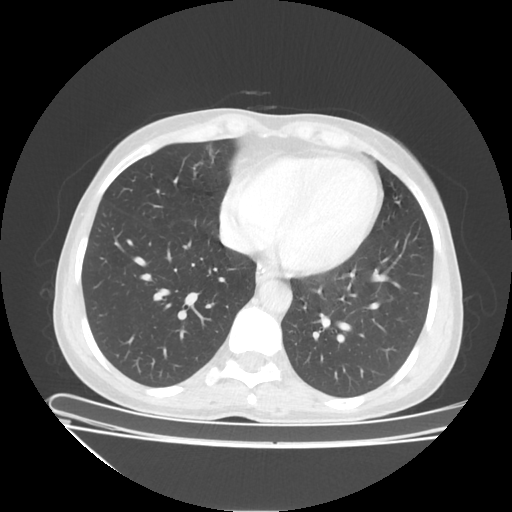

Image Grid

4×3 grid: Rows show different image types (Original NATIVE, Reconstructed NATIVE, Original VENOUS, Generated VENOUS), Columns show windowing techniques (No Window, Lung Window, Mediastinum Window)

Generated VENOUS CT scan (A→B translation)

No window - Raw intensity values

Generated VENOUS CT scan (A→B translation)

Lung window (WL -600, WW 1500 → Low −1350, High +150)

Generated VENOUS CT scan (A→B translation)

Mediastinum window (WL 40, WW 400 → Low −160, High +240)

Windowing Parameters

- No Window: Raw intensity values without windowing

- Lung Window: WL -600, WW 1500 → Low −1350, High +150 (optimal for pulmonary structures)

- Mediastinum Window: WL 40, WW 400 → Low −160, High +240 (optimal for soft tissues)